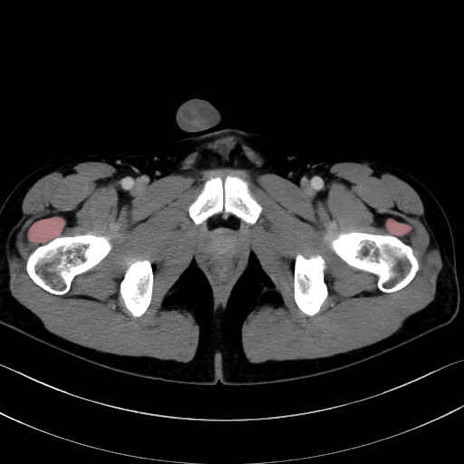

外側広筋(vastus lateralis) のCT画像の解剖

外側広筋 (Vastus lateralis)